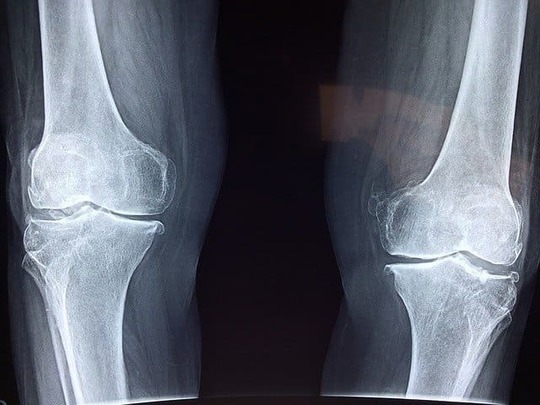

軽い打撲の場合は、約1〜2週間で腫れや痛みはおさまります。しかし、場合によっては骨折していたり、体の中の器官までダメージを受けることがあります。最悪の場合、麻痺が残ったり呼吸困難が起こったりすることもあるため注意が必要です。

軽い打撲の場合は市販薬で改善しますが、重い打撲の場合は骨折をしていたり体の中の器官が損傷を受けている可能性もあります。痛みが軽い場合も念の為病院に行くことをお勧めいたします。